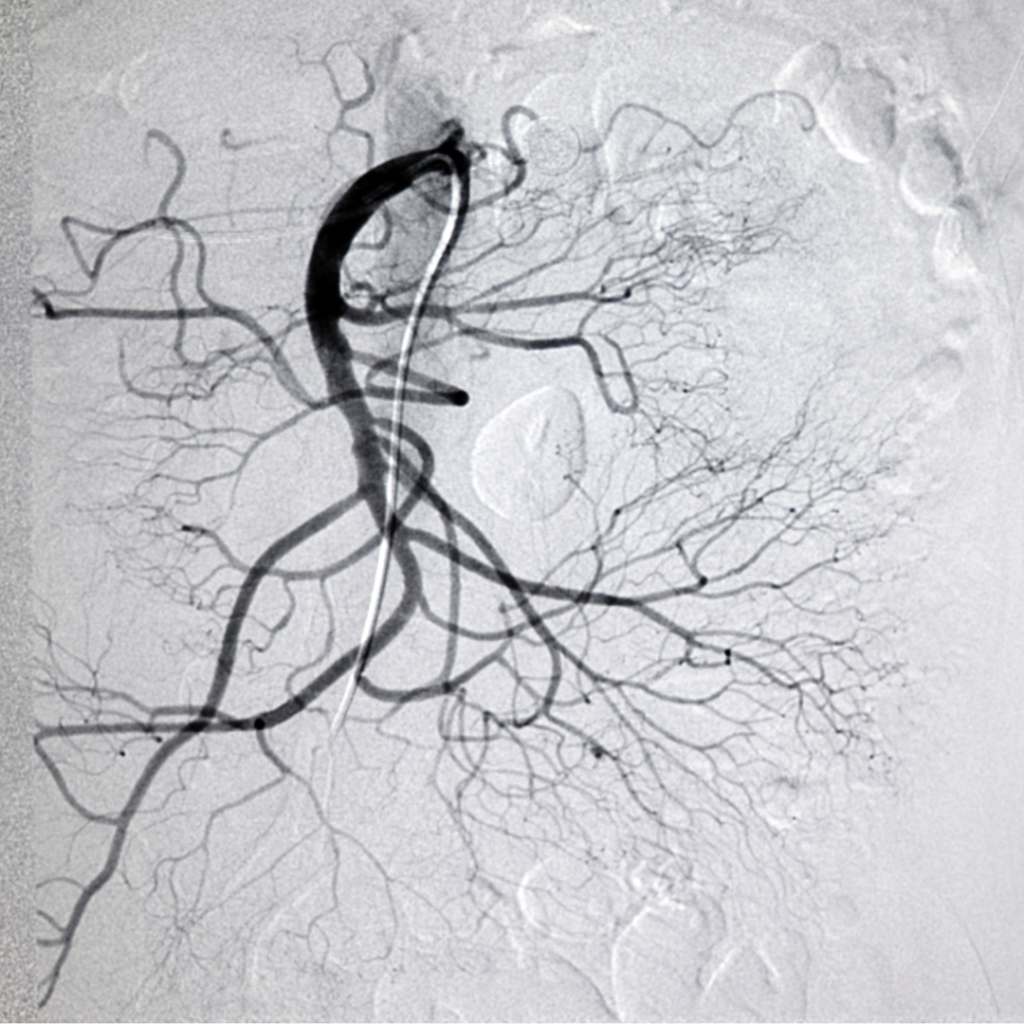

La circulacion arterial mesenterica se caracteriza por su abundante circulacion colateral. Las tres arterias mesentericas principales proporcionan perfusion arterial al tubo digestivo:

- el tronco celiaco.

- la arteria mesenterica superior.

- la arteria mesenterica inferior.

En general el tronco celiaco proporciona circulacion arterial al intestino anterior que va desde la porcion distal del esofago hasta el duodeno, sistema hepatobiliar y bazo; a arteria mesentérica superior proporciona irrigacion al intestino medio que va desde el yeyuno hasta el mesocolon; y la arteria mesentérica inferio que irriga al intestino posterior que incluye mesocolon transverso hasta el recto.

El tronco celiaco y la arteria mesdntérica superior se originan de la superficie ventral de la aorta abdominal suprarrenal infradiafragmatica, en tanto que la arteria mesentérica inferior se origina de la porcion lateral izquierda de la aorta infrarrenal.

Cuando hay una oclusion aguda de un tronco mesenterico principal puede ocasionar isquemia grave por falta de flujo colateral suficiente. La red colateral entre el tronco celiaco y la arteria mesentérica superior existe principalmente a traves de las arterias pancreaticoduodenales superior e inferior.

La arteria mesentérica inferior puede proporcionar flujo arterial colateral a la arteria mesentérica superior a traves de la arteria marginal de Drummond, el arco de Riolano y otros vasos retroperitoneales colaterales sin nombre denominados arterias mesentericas tortuosas.

Los vasos viscerales colaterales pueden proporcionar importante flujo arterial a la arteria mesentérica inferior y el intestino posterior a traves de las arterias hipogastricas y la red arterial hemorroidal.